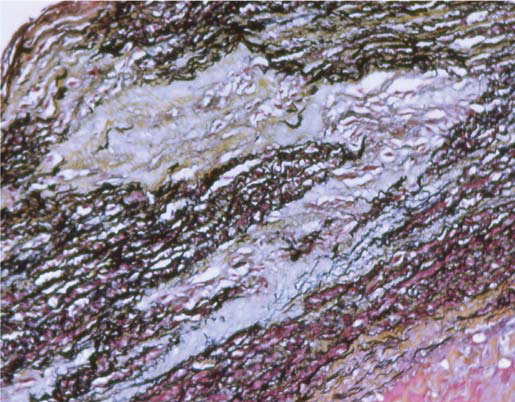

Autopsy shows a section of the aortic wall stained with aldehyde fuchsin. The patient experienced a fatal aortic dissection. What is shown in this section?

Metachromatic material characteristic of cystic medial necrosis of Erdheim